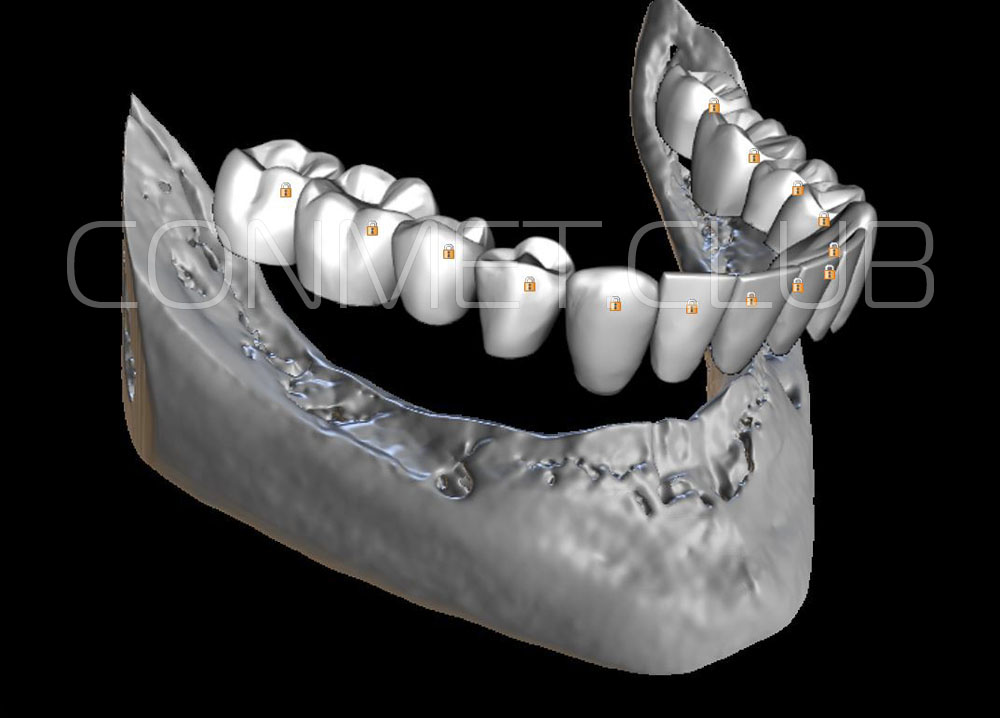

Посмотрите на небольшом клиническом примере новый подход к конструированию имплантата по сравнению с имплантатами описанными в начале этой статьи.

Первый вывод к которому мы пришли, это то, что для данных конструкций имплантатов сохранять внутренний интерфейс с шестигранником и конусом Морзе нецелесообразно из-за ограничения возможностей современной 3D печати титана. Кроме того, техническая обработка после 3D печати такого интерфейса представляет значительные трудности и ведет к неоправданному увеличению цены. Поэтому пришли к единодушному мнению, что лучший вариант-это опорные элементы полностью повторяющие абатменты-мультиюниты.

Второй, и наверное главный вывод-решение - моделированием и конструированием индивидуальных, субпериостальных имплантатов должен заниматься инженер-конструктор с большим опытом в медицине и знаниями индивидуальной анатомии челюстно-лицевой области на уровне хорошего хирурга. При этом все-равно должно осуществляться тесное и постоянное взаимодействие с хирургом, который будет проводить операцию.

Посмотрите на приведенные выше работы и вы обратите внимание, что перфорации в теле имплантатов подчиняются скорее "художественным" принципам нежели биомеханическим. Поэтому уже в 2018 году не только изготовление, но и конструирование имплантатов было целиком передано сотрудникам Конмет. Это в значительной степени повысило качество самих имплантатов, но по вполне понятным причинам (таких грамотных инженеров-конструкторов по определению не может быть много) резко удлинились сроки изготовления. При определенных случаях, когда после удаления зубов кость еще не окончательно закончила ремоделировку, срок с момента КТ по которому моделируют субпериостальный имплантат, до операции может носить критический характер. Т.е., чем дольше время изготовления, тем больше вероятность того, что имплантат не полностью будет соответствовать рельефу подлежащей костной ткани.